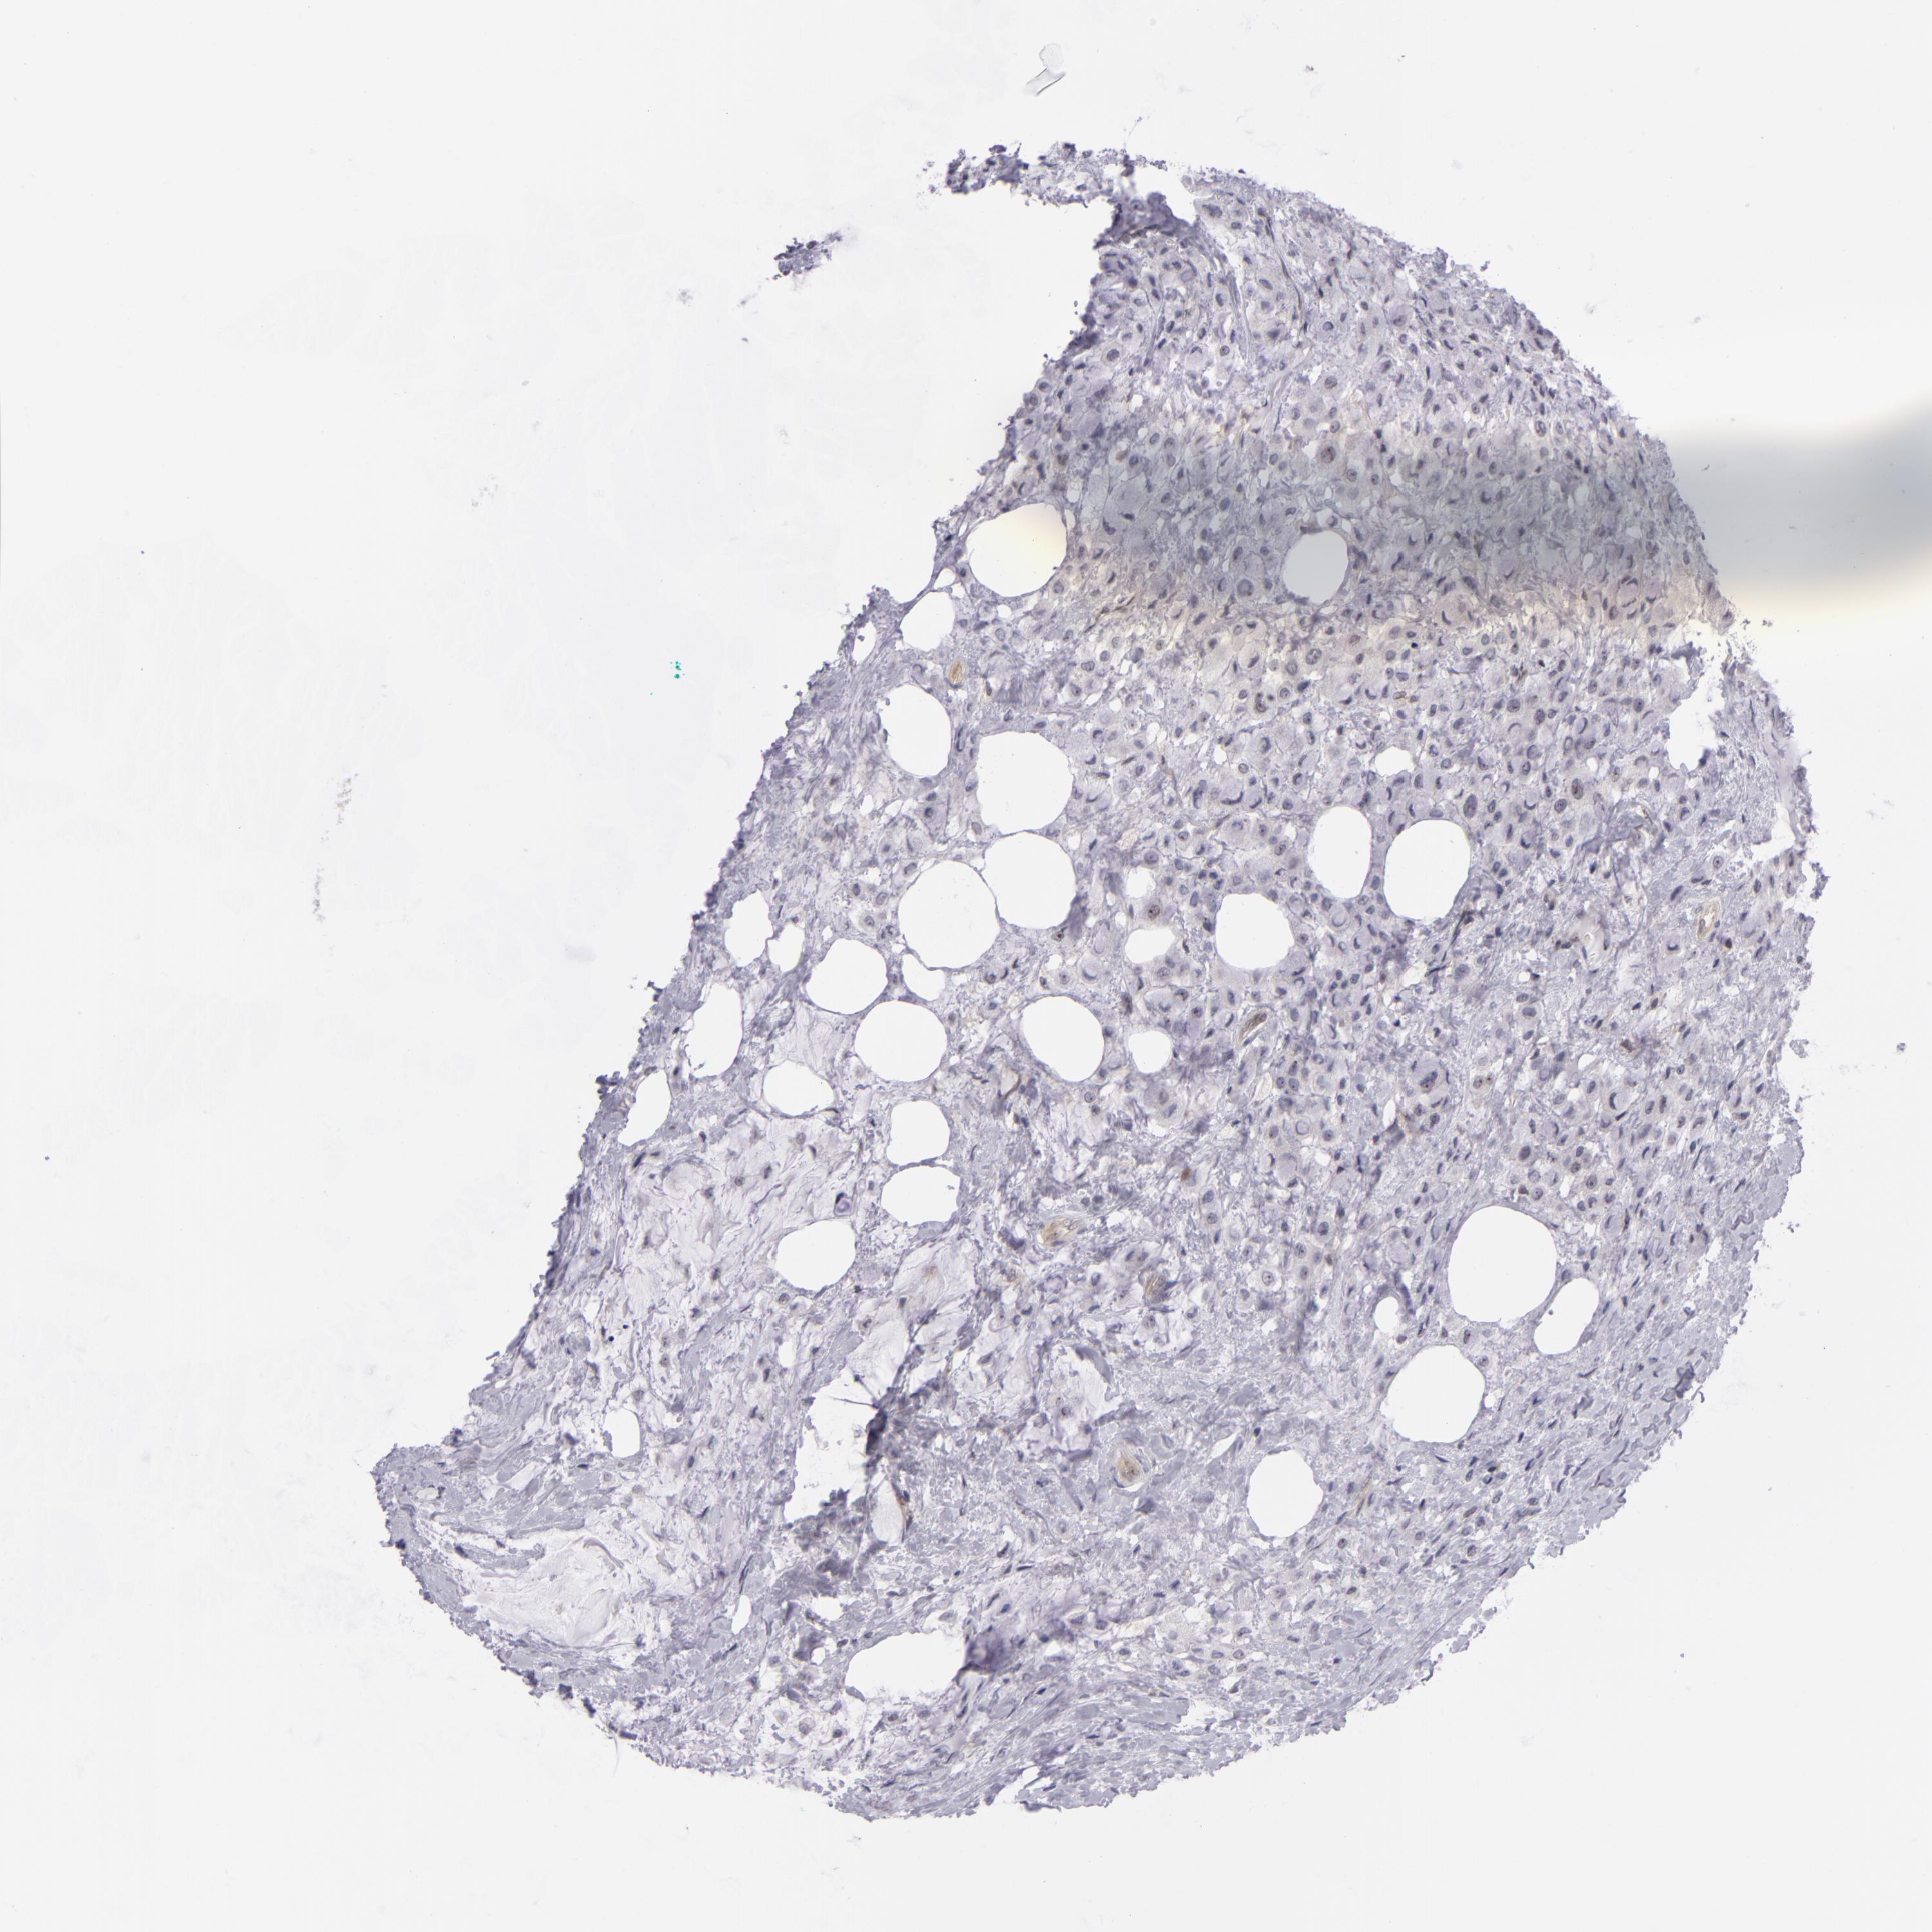

BRCA TCGA BRCA VALIDATION PROTEIN EXPRESSION

ANTIBODIES

AND

VALIDATION